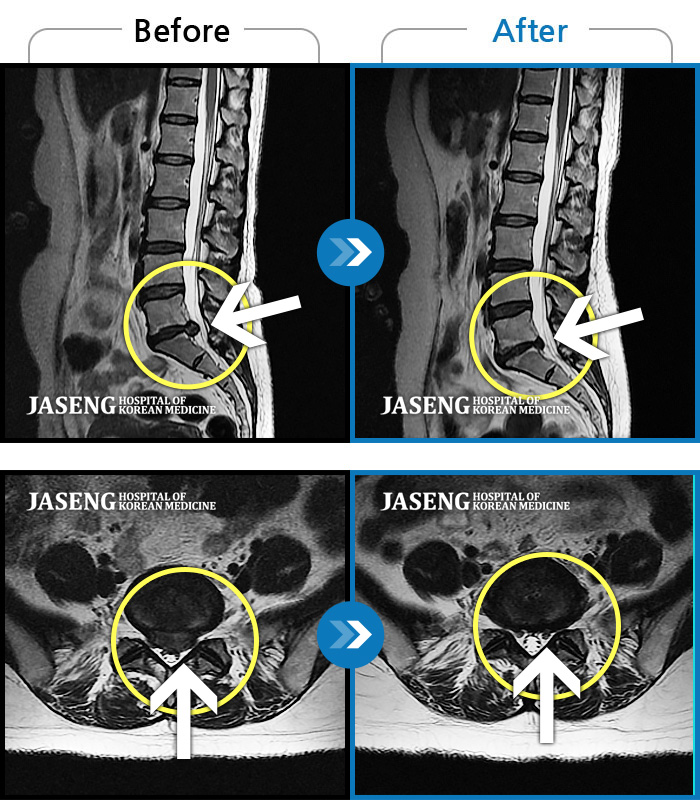

허리디스크

안산 · 김민수 원장

발목의 힘이 떨어져서 절뚝거리면서 걸었다.

촬영시기

2022.01.03 ~ 2024.07.31

2024.08.09